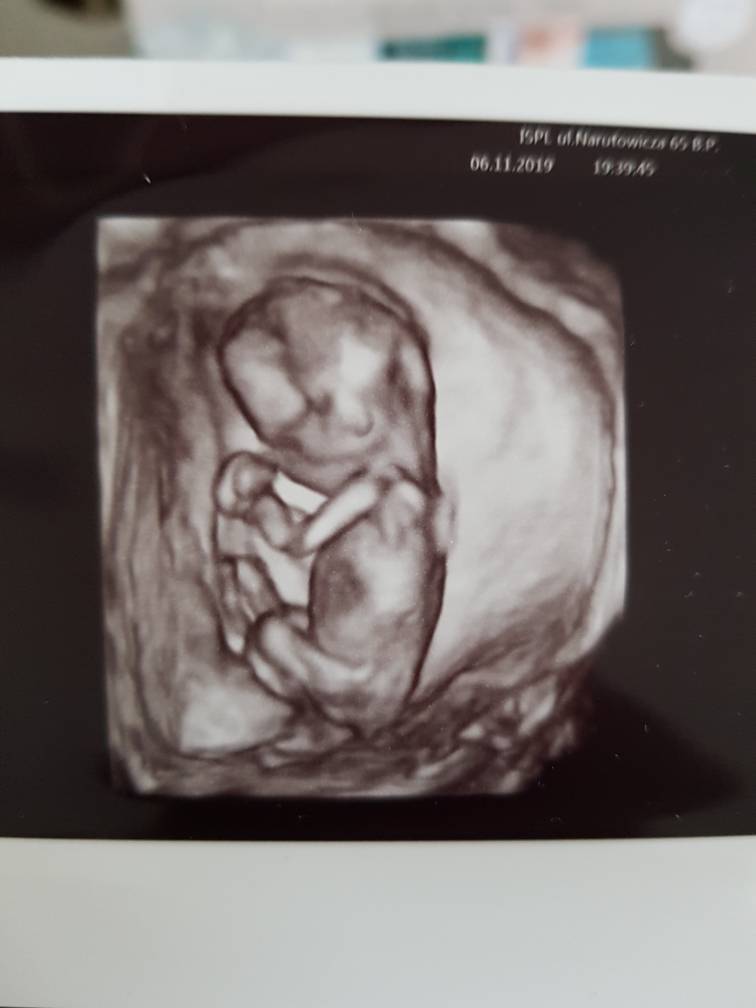

Poprosiłam lekarza, żeby nie podawał płci dziecka. Tylko żeby napisał na kartce i zawinął tak, żeby nie było widać. Lekarz się śmiał, że nie wytrzymam i w drodzę podejrzę. Ale dałam radę i nie podglądałam, w domu otworzyliśmy karteczkę razem z mężem. W zdjęciach wstawiam tą karteczkę oraz zdjęcia z usg. Niestety nie dostałam zdjęcia 2d z zaznaczoną długością malucha, jedynie 3d. Z tego co pamiętam to lekarz mówił, że długość dziecka odpowiada 15 tyg., a wczoraj według om zaczęłam 16 tydzień. [emoji6]Zobacz załącznik 1042359Zobacz załącznik 1042362